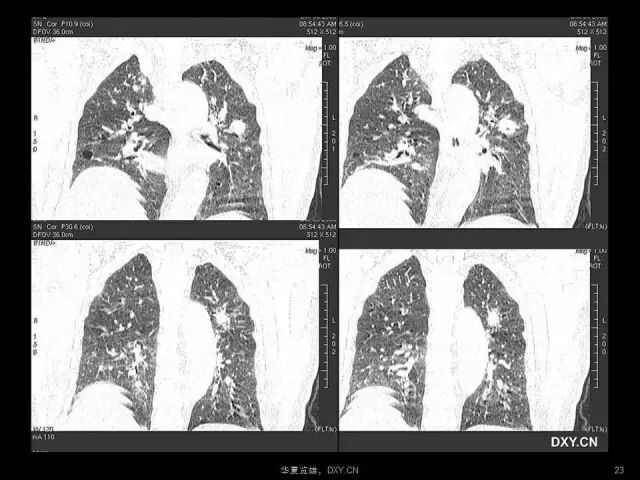

肺炎、肺癌、肺结核在影像学上的征象往往千变万化。